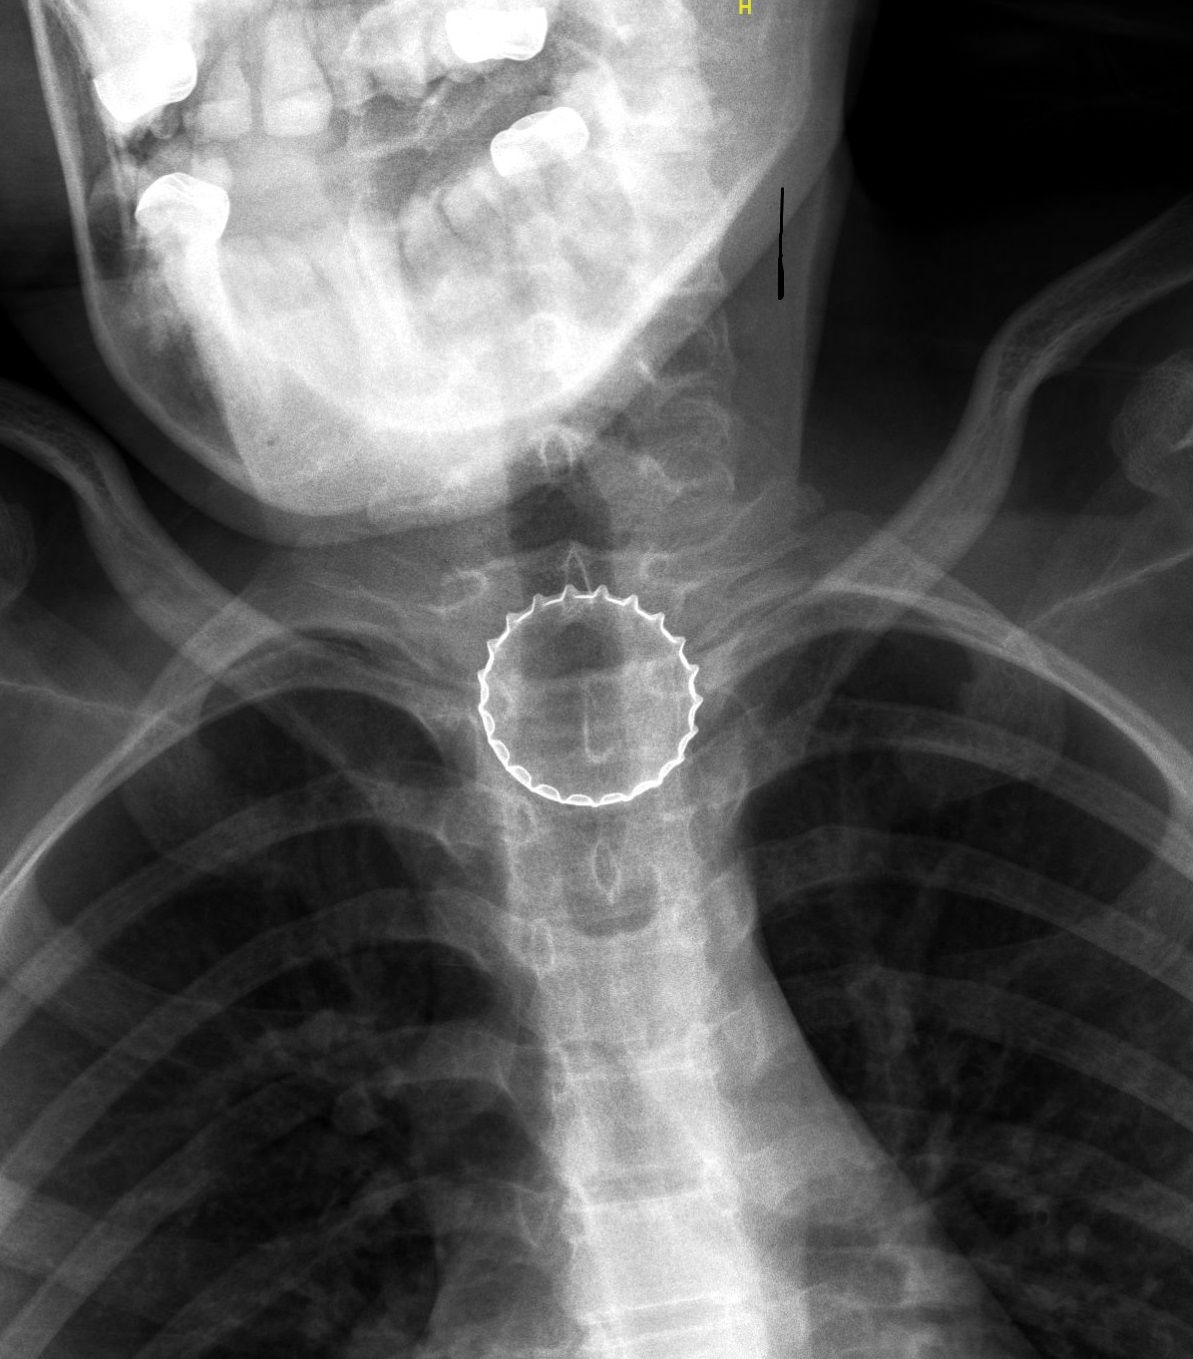

נערה בת 14 הגיעה לטיפול במרכז הרפואי לגליל, כשהיא מתלוננת על קושי בבליעה וכאבי גרון. לאחר צילום, התברר כי היא בלעה פקק של בקבוק בירת קורונה, שהוצא ע"י צוות אף אוזן גרון באמצעות ציוד אנדוסקופי.

ד"ר עלי ח'טיב, מומחה ברפואת ילדים, בדק אותה ביסודיות, ובין השאר בוצע לה צילום רנטגן, בו התגלה גוף זר בוושט. הנערה הוכנסה לחדר ניתוח, שם - באמצעות ציוד אנדוסקופי ייעודי - הוצא מצינור הוושט פקק של בירה קורונה ע"י צוות ממחלקת אף אוזן גרון וניתוחי ראש-צוואר, בניהולו של ד"ר אייל סלע. הנערה אושפזה להשגחה למשך יממה ושוחררה במצב טוב.